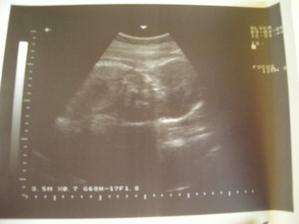

Tak máme za sebou utz, bobíček je v pořádku, pěkně nám vyrostl, máme cca 2100g,jsme hlavičkou dolů a odpovídáme 32+0...jen tak dál🙂)